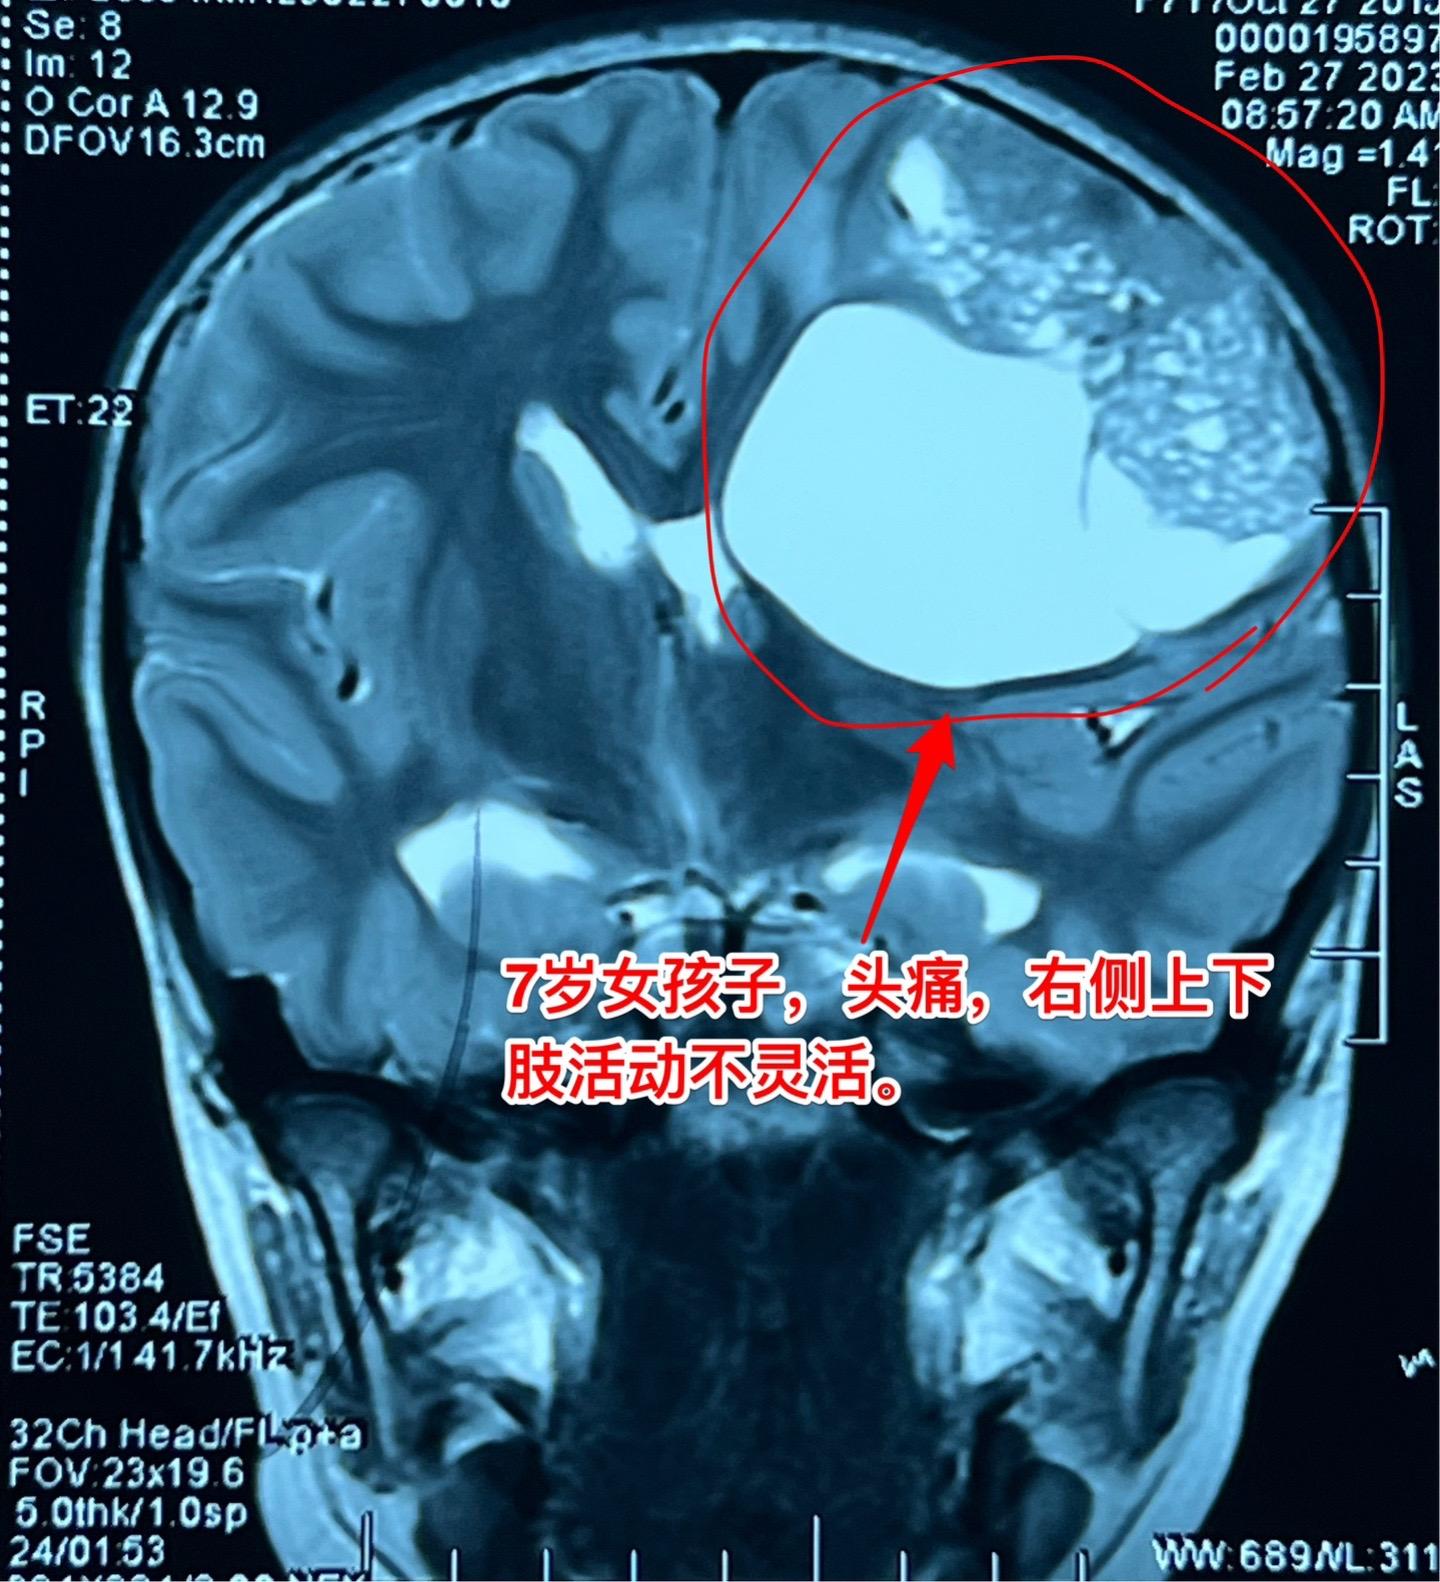

高级别胶质瘤手术后22个月,定期复查。2023年2月28日邯郸市7岁的小女孩因右侧上下肢无力在我科行开颅手术,切除左侧大脑的巨大肿瘤。如图所示,肿瘤体积巨大,手术后小女孩右侧上下肢无力症状明显改善。 病理报告为神经上皮肿瘤WHO三级。手术后作了全脑放疗。 今天是手术后22个月复查,肿瘤没有复发,小孩子的四肢活动无力弱,能正常上学。磁共振显示肿瘤没有复发,以后还要定期复查。